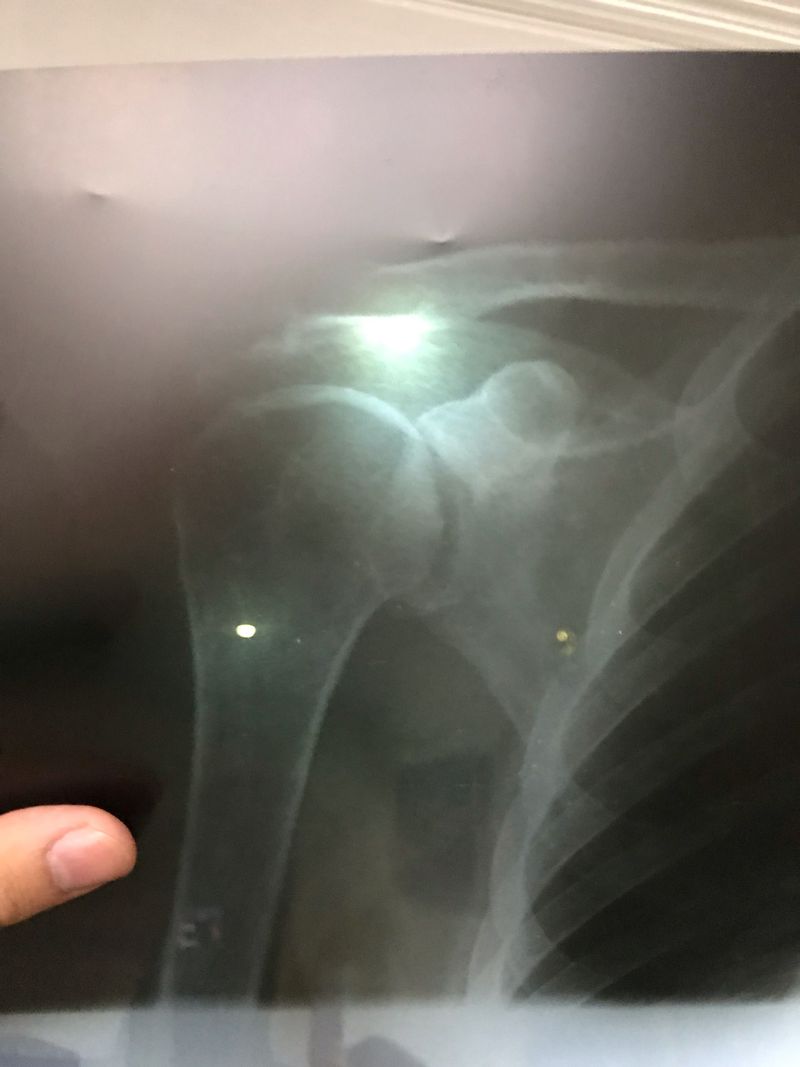

A 71-year-old woman came to the hospital with a pain in the right shoulder. He has renal dysfunction and he should be dialyzed 4th in month ;but did not arbitrarily dialysis. After a month, the BUN were 81 and 6 keratin. He was suffering from poisoning with urea and had a drowsy condition. He was prescribed immediate dialysis with sodium serum. After 4 times continuous dialysis, BUN decreased to 27 and Creatine 2. PTH 540 and level of calcium and vitamin D levels were not good . A metastatic diagnosis of calcification was given. Calcium tablets are consumed. And after two weeks, the shoulder was discounted, but the PTH level is high. What is your discretion? Parathyroid cancer? Tumor Kidney problems?